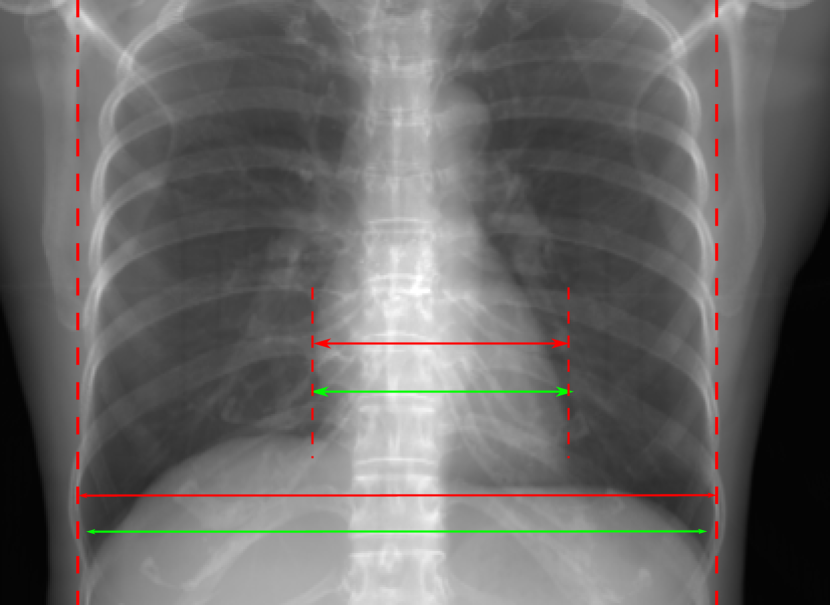

5.1 Chest Data

Refer to caption

(a) Reference

(b) 0superscript00^{\circ} perspective

(c) (b)-(a)

0.4237, -, -

0.4002, 17.01, 0.6532

Pix2pixGAN

(d) 0superscript00^{\circ} Cartesian

(e) 0&180superscript0superscript1800^{\circ}\&180^{\circ} Cartesian

(f) 0&180superscript0superscript1800^{\circ}\&180^{\circ} polar

0.4303, 7.08, 0.8535

0.4214, 5.37, 0.9098

0.4240, 3.83, 0.9536

(g) (d)-(a)

(h) (e)-(a)

(i) (f)-(a)

TransU-Net

(j) 0superscript00^{\circ} Cartesian

(k) 0&180superscript0superscript1800^{\circ}\&180^{\circ} Cartesian

(l) 0&180superscript0superscript1800^{\circ}\&180^{\circ} polar

0.4272, 10.92, 0.8222

0.4281, 9.37, 0.8424

0.4248, 8.12, 0.8859

(m) (j)-(a)

(n) (k)-(a)

(o) (l)-(a)

Figure 10: Perspective deformation learning in one exemplary patient case for chest X-ray imaging. The maximal horizontal cardiac diameter and the maximal horizontal thoracic diameter in (b) and (d)-(f) are indicated by the horizontal red lines, while those in the reference image (a) are green lines. The cardiothoracic ratio, RMSE, and SSIM for each image is displayed in its corresponding subcaption.

TABLE II: Quantitative evaluation of different methods on chest data.

Method Metric 0superscript00^{\circ} input 0superscript00^{\circ} 0&180superscript0superscript1800^{\circ}\&180^{\circ} 0&180superscript0superscript1800^{\circ}\&180^{\circ}

perspective Cart. Cart. polar

Pix2pix RMSE 18.68 11.88 7.90 4.98

GAN SSIM 0.6401 0.8103 0.8944 0.9493

Trans RMSE 18.68 17.21 12.12 13.06

U-Net SSIM 0.6401 0.7744 0.8950 0.8899

The results of one patient in chest X-ray imaging are displayed in Fig. 10, where the cardiothoracic ratio is assessed as an exemplary clinical application [32]. In the reference image (Fig. 10(a)), the maximal horizontal cardiac diameter (MHCD) and the maximal horizontal thoracic diameter (MHTD) are indicated by two green horizontal lines. Its cardiothoracic ratio is 0.4237. In the 0superscript00^{\circ} perspective projection image (Fig. 10(b)), all the anatomical structures can be visualized with fine resolution. However, due to perspective deformation, anatomical structures, e.g. the ribs and the spine, are deformed. The deformations are visualized better in the difference image Fig. 10(c). Compared with the ribs and the spine, the heart has less deformation as its location is closer to the isocenter. In Fig. 10(b), the MHCD and the MHTD are indicated by two red horizontal lines, while the green lines are those of the reference image. While the MHCD has changed little from 10.47 cm to 10.16 cm, the MHTD has changed considerably from 24.71 cm to 25.40 cm. As a consequence, the cardiothoracic ratio becomes 0.4002, which is below the normal range of 0.42 - 0.50 [32]. The result of learning perspective deformation from 0superscript00^{\circ} single view is displayed in Fig. 10(d), where the MHCD and the MHTD are 10.63 cm and 24.71 cm, respectively. The MHTD of Fig. 10(d) is the same as that of the reference image. This is also reflected by the difference image Fig. 10(g), where the lower ribs have small errors. However, the upper ribs as well as the spine still have considerable errors. The results of perspective deformation learning from 0&180superscript0superscript1800^{\circ}\&180^{\circ} views in Cartesian and polar coordinates are displayed in Fig. 10(e) and Fig. 10(f), respectively. The measured MHCDs and MHTDs in these two images are very close to the reference ones. Hence, their cardiothoracic ratios, 0.4214 and 0.4240 respectively, are close to the reference ratio as well. In the difference images (Fig. 10(h) and Fig. 10(i)), the errors of ribs and spine decrease as their boundaries are no longer apparently visible. Nevertheless, Fig. 10(i) has less error than Fig. 10(h), achieving the smallest RMSE value of 3.83. The quantitative evaluation of all the 162 testing datasets is displayed in Tab. II, where learning perspective deformation from two complementary views in polar coordinates achieves the least RMSE 4.98 and highest SSIM 0.9517, demonstrating the superiority of learning perspective deformation from two complementary views in polar coordinates.

The TransU-Net results are displayed in Figs. 10(j)-(l). Compared with their corresponding Pix2pixGAN results, the TransU-Net prediction images are more blurry, although the same perceptual loss is used. The error images in Figs. 10(m)-(o) indicate that TransU-Net reduces perspective deformation better with complementary views than a single view. The quantitative evaluation in Tab. II shows that TransU-Net cannot effectively reduce perspective deformation with a single view. With complementary views in both Cartesian and polar coordinate systems, TransU-Net achieves comparable performance, which is still considerably worse than that of Pix2pixGAN. The inferior performance of TransU-Net to Pix2pixGAN on the chest data is potentially caused by the repetitive nature of the segmental rib anatomy, which leads TransU-Net to be ineffective in extracting position-dependent features.